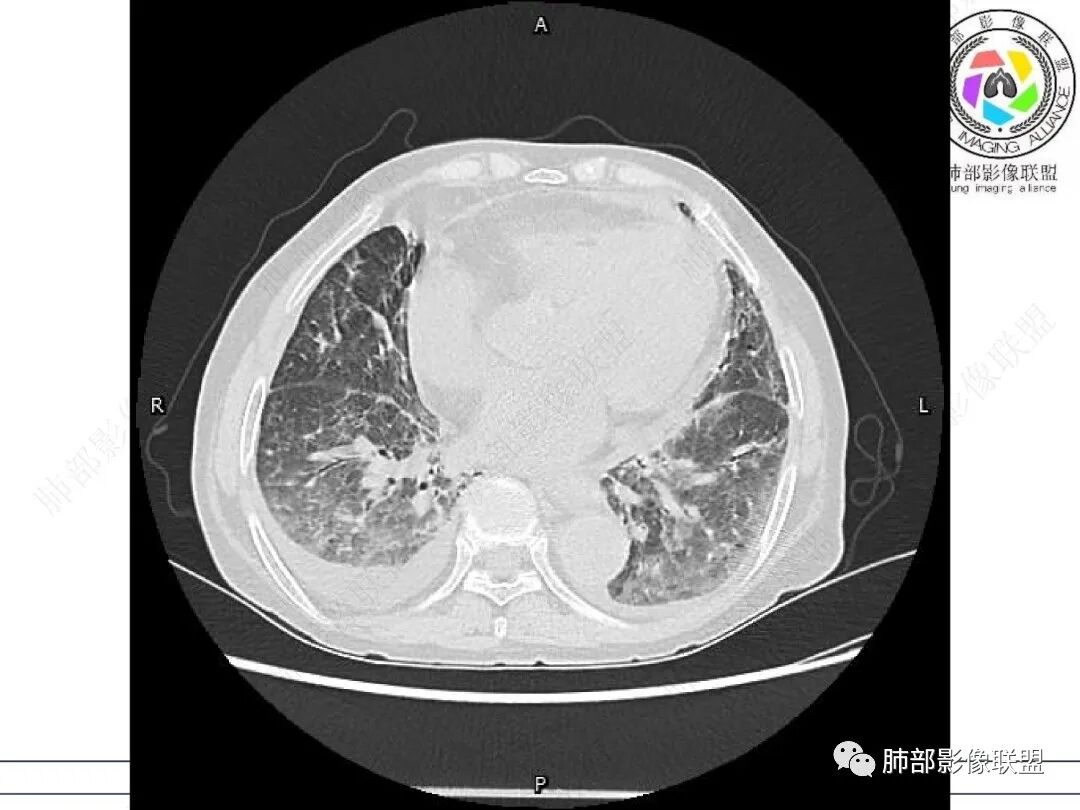

老年女性,类风湿关节炎病史多年。发热。以两肺下叶为主弥漫磨玻璃及网格状透亮影,透亮度减低,局部小蜂窝状改变;两肺胸膜下散在几枚实性病灶;双侧胸腔积液。考虑RA-ILDNSIP

双肺下叶多发蜂窝影,双肺小叶间隔增厚,双肺磨玻璃影,双侧胸腔积液,有类风湿性关节炎,考虑结缔组织相关性间质性肺病,合并感染

①影像表现复杂:较弥漫间质性改变,对称磨玻璃密度为主,小叶间隔增厚,有一定重力分布趋势,未见明显纤维化,气囊及蜂窝位于肺边缘,未见典型“月弓征”。心脏影增大,双侧胸腔积液。

这即可见于间质性肺病,也可见于真菌感染(如PJP)、病毒感染,类风湿,以及肺水肿等等。

一般而言,如存在磨玻璃密度影浑浊,有重力分布趋势,肺表面蜂窝影,胸腔积液等等,并不常见于单纯PJP,除非其他因素叠加。

上肺斑片影、结节影,夹杂纤维条索影,边界清楚,新旧不等,胸膜牵拉明显等等,符合较典型继发性肺结核表现,但它却未必是此次就医主要责任病原体!